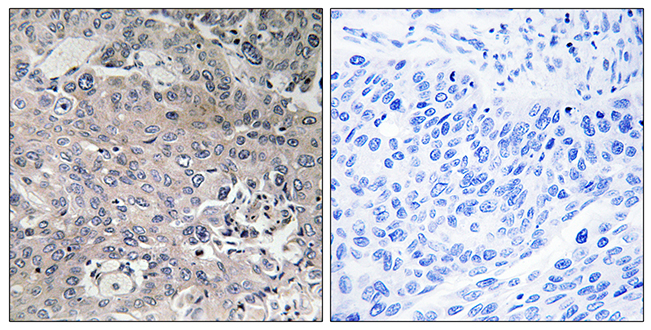

Anti-ABCD4 AntibodyA97755

ApplicationsWestern Blot, ELISA, ImmunoHistoChemistry

ReactivityHuman, Mouse